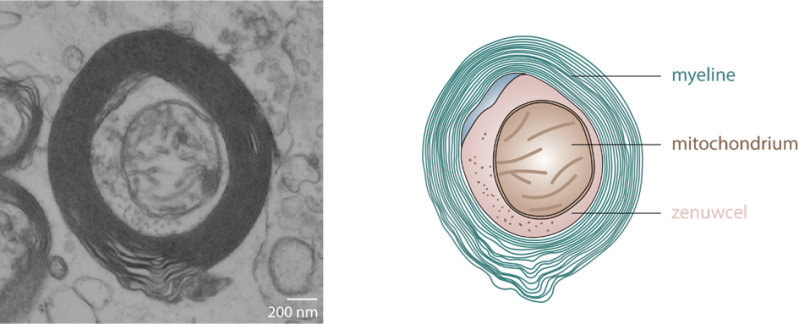

Voor de analyse van het weefsel heb ik mij in eerste instantie gefocust op drie dingen, namelijk de zenuwcellen, de beschermende myeline laag om de zenuwcellen en de mitochondria (zie plaatje). Zoals jullie weten wordt MS wordt gekenmerkt door beschadiging van de beschermende myeline laag. De myeline is nog wel aanwezig in de normaal uitziende witte stof van mensen met MS. Myeline is niet alleen essentieel om zenuwprikkels snel en efficiënt over te dragen, maar ook om de zenuwdraad van voedingsstoffen te voorzien. Op het moment dat de myeline laag beschadigd raakt, heeft de zenuwcel meer energie nodig. Mitochondria, de energiefabriekjes van de cel, gaan dan aan de slag en voorzien de zenuwcellen van deze extra energiebehoefte. Hierdoor zijn er ook meer mitochondria aanwezig in de zenuwdraden in witte stof MS laesies. De eerste bevindingen van de analyse tonen aan dat er niet iets met de myeline dikte veranderd, maar wel met de kenmerken van de zenuwdraden. Hopelijk kan ik jullie in de volgende blog hier wat meer in detail over vertellen.

Een zenuwcel met een beschermlaagje myeline en een mitochondrium (= energiefabriekje). Links een plaatje gegenereerd met behulp van elektronenmicroscopie, rechts een schematische weergave van dezelfde zenuwcel met myeline en een mitochondrium.